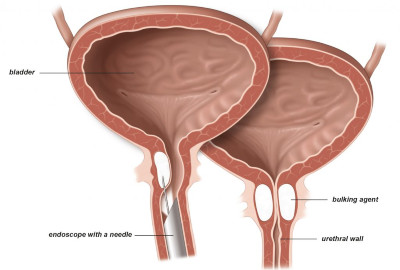

Θεραπευτικές Επιλογές